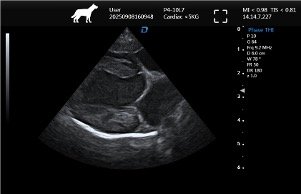

| Imaging Quality | Clear 2D, stable grayscale, optional Color Doppler for abdominal, cardiac, reproductive exams | Ensure system covers most frequent clinical exams |

Common Clinical Applications

▸ Basic cardiac screening